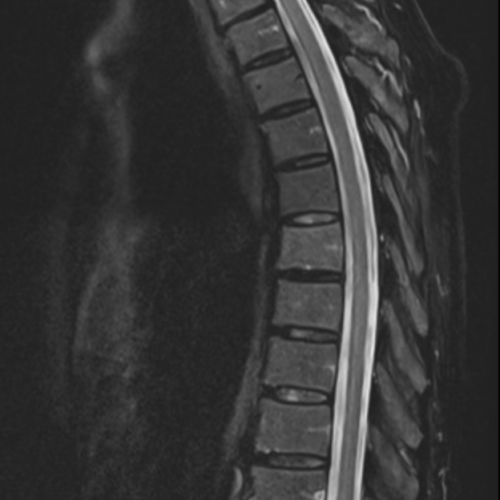

Cet examen est réalisé pour analyser la moëlle épinière, le cîne terminal en cas de paresthésies, troubles sensitifs ou moteurs d’un membre, suivi de SEP sclérose en plaque.

Quels sont les résultats possibles d’une IRM de la moelle épinière ?

Cette examen permets de diagnostiquer:

- les plaques démyélinisantes

- les fistules durales

- les compressions médullaires

- les tumeurs médullaires (épendymomes, astrocytome)

- les cavernomes médullaires

- les myélopathies infectieuses, inflammatoires

- les leptoméningites infectieuses ou carcinomateuses